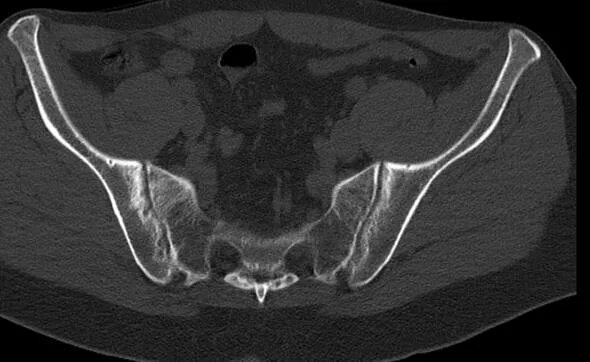

Сакроилеит на кт